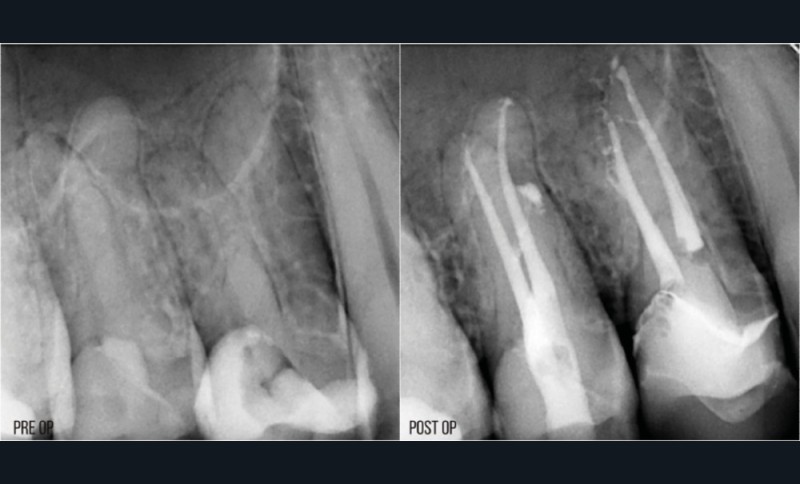

La condensation verticale à chaud est la technique d’obturation de référence. Elle nécessite de compacter la gutta-percha jusqu’à environ LT-4 mm avec un fouloir manuel. Avec les préparations conservatrices, il sera parfois difficile d’atteindre cette longueur, même avec le plus fin des fouloirs. Si on prend par exemple une préparation à 25/.04, le diamètre à LT-4 mm sera de 0,41 mm. Le fouloir le plus fin ayant un diamètre de 0,4 mm, il y a de forts risques de contact latéral avec les parois canalaires s’il atteint LT-4 mm, qui pourrait provoquer un effet de coin. Si le canal est courbe, il sera impossible d’amener le fouloir à la longueur souhaitée (fig. 17).

La condensation latérale à froid impose de pouvoir placer un spreader à LT-2 mm. Avec une préparation plus fine, il sera compliqué d’atteindre cette longueur, notamment s’il y a des courbures. C’est aussi une technique qui génère d’importants stress au niveau radiculaire, exposant la racine à un risque plus élevé de fracture [35]. Avec une préparation préservatrice, il y aura plus de contacts entre le spreader et la paroi dentinaire, et potentiellement une augmentation du risque de fracture (fig. 18).

La thermo-compaction nécessite un instrument rigide, le thermocompacteur, qu’il faut faire travailler à LT-2 ou 3 mm. Le même problème qu’avec les spreaders se posera niveau des canaux courbes. Avec une préparation plus étroite, on aura également plus de risque de contact entre l’instrument en rotation et les parois canalaires. Cela pourrait conduire à un échauffement radiculaire important et de possibles répercussions sur le parodonte en regard [36] (fig. 19).

La gutta sur tuteur est utilisable en théorie à partir du moment où il existe un tuteur adapté au système de mise en forme. En pratique, la visibilité pourra être compliquée s’il y a plusieurs canaux à obturer, surtout dans le cas d’une cavité d’accès conservatrice (fig. 20).

La technique dite « monocône » est la meilleure pour obturer les préparations conservatrices, dans la mesure où il sera toujours possible d’ajuster un cône de gutta-percha adapté à la longueur de travail (fig. 21). C’est aussi la plus simple à mettre en œuvre. Mais est-ce une bonne technique d’obturation ? Dans les techniques d’obturation classiques, la gutta-percha est utilisée comme matériau de remplissage, celui qui occupera en majorité le volume de l’endodonte. Comme la gutta n’a aucune propriété d’adhésion à la dentine, il faut lui adjoindre un matériau de scellement : le ciment. Ce ciment représente pourtant la faiblesse de l’obturation. D’une part parce qu’il est soumis à une rétraction lors de sa prise [37] et, d’autre part, parce que, même après la prise, il reste sensible à l’hydrolyse [38]. La dégradation du joint de ciment est donc inéluctable. Pour minimiser l’impact sur la qualité de l’obturation et de l’étanchéité, le volume de ciment doit être le plus faible possible.

Avec la technique monocône, il n’est pas possible d’obtenir un volume de ciment suffisamment faible pour garantir une obturation étanche dans le temps [39], et ce même si le cône de gutta-percha est ajusté. En cela, la technique monocône, utilisée avec un ciment de scellement classique, ne peut pas être considérée comme une bonne technique d’obturation.